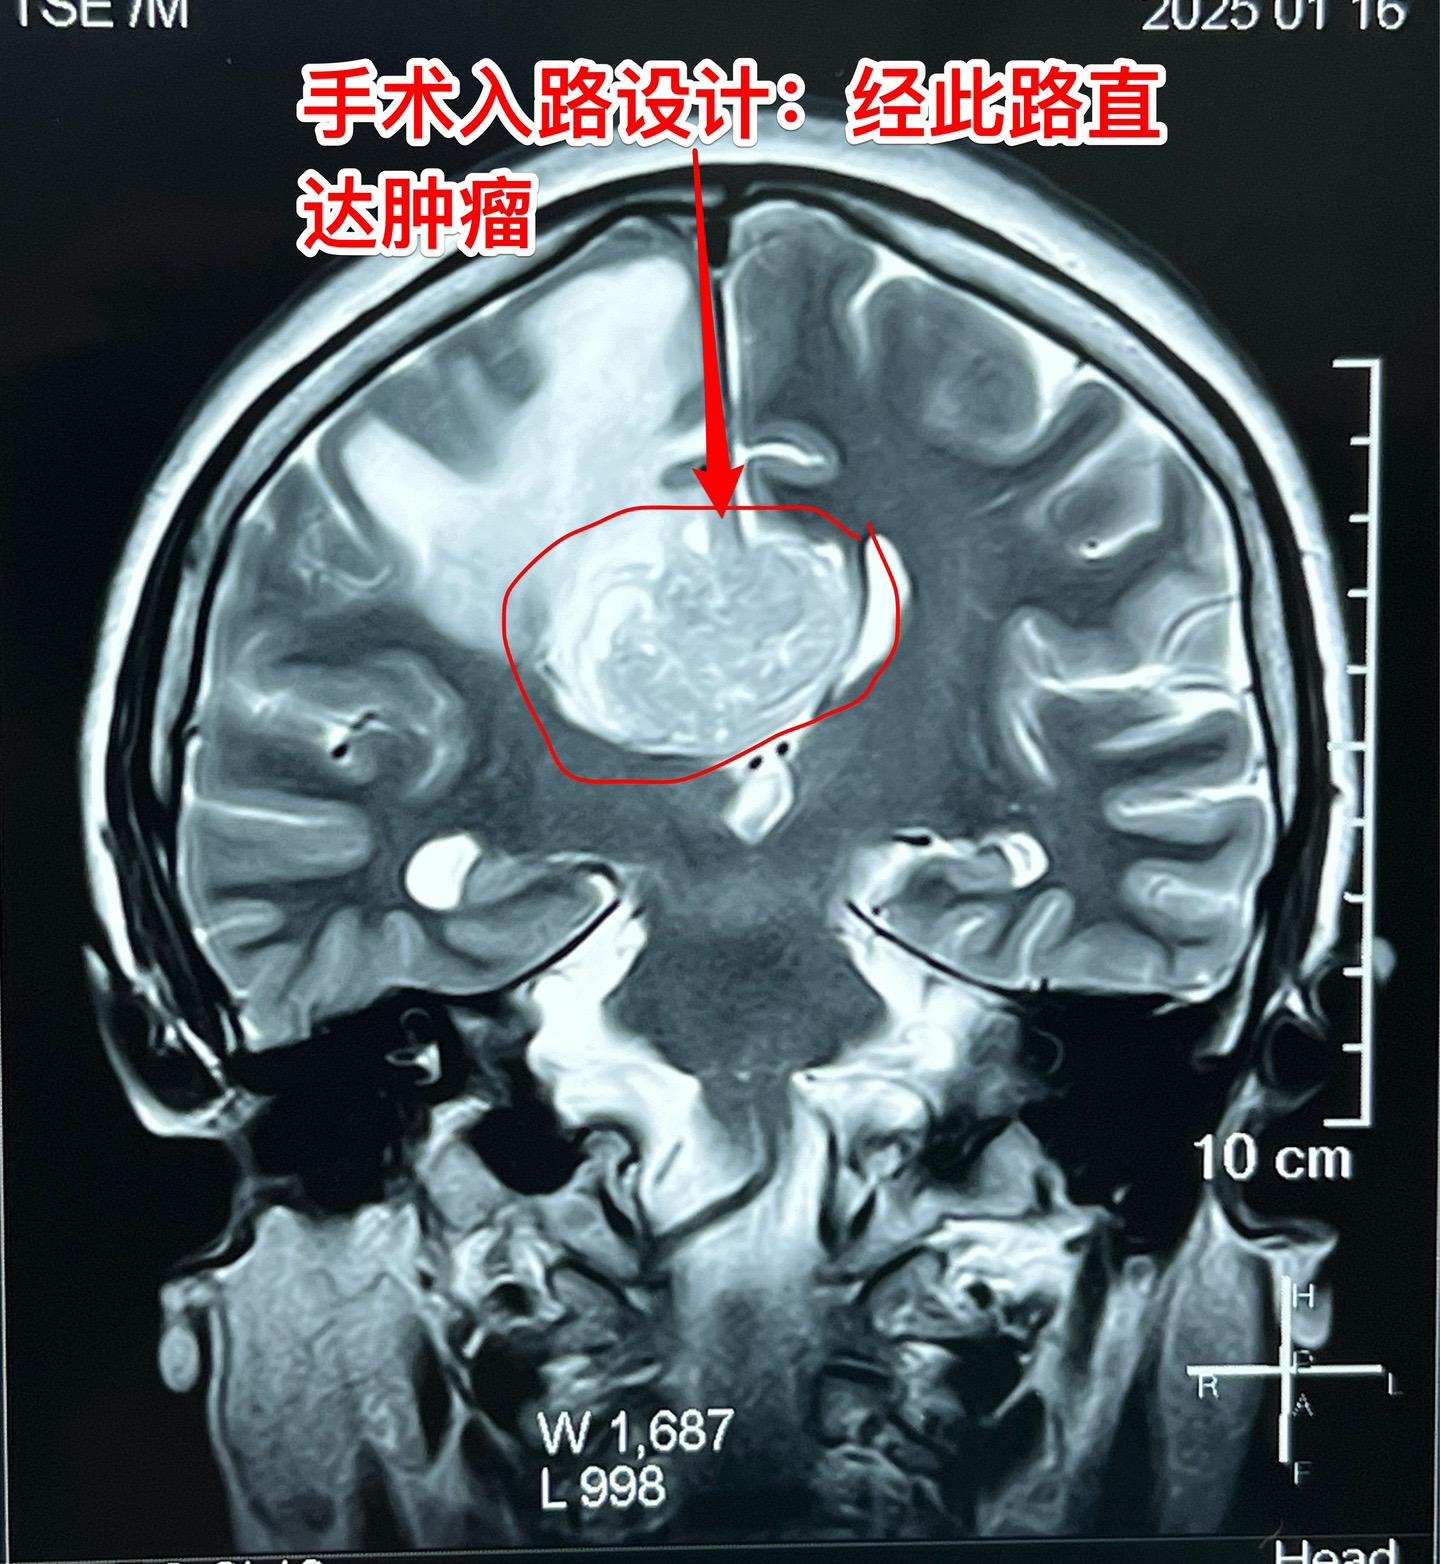

乳腺癌也能转移到脑部。脑部的转移瘤约80%来源于肺癌,绝大多数是腺癌。 乳腺癌发病率虽然低于肺癌,但也很常见。乳腺癌也可能转移到脑部。 这个54岁女性在7个月前先发现 脑部有个瘤,随后发现了乳腺癌,作了乳腺癌切除手术及内分泌治疗。多次复查磁共振显示脑部的瘤体积在增大,而且病人也出现头痛症状,故来作手术。 1月23日作了手术,顺利切除肿瘤。术前病人担忧出现偏瘫症状,手术后并没有出现。 针对这个病随后还需要综合治疗。